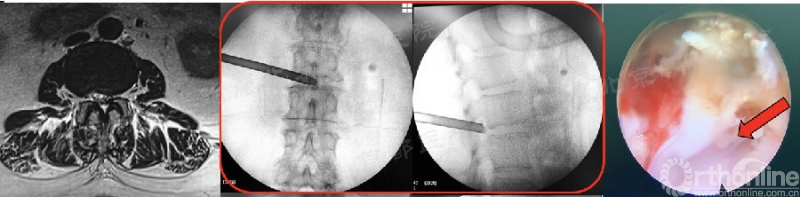

b. 第91例,第一次神经损伤,也希望是最后一例。

第91例,L2/3节段I-2-a区LDH。在置管后患者诉左下肢屈髋较对侧无力,无下肢放射痛及麻木,术中透视如图(红框)所示。镜下摘除髓核后将工作通道朝向背侧观察神经,患者诉颈部疼痛(脊髓高压症),镜下发现硬膜缺损(红箭头),但神经结构完整。立即结束手术。术后髂腰肌肌力IV级,大腿前方感觉减退,术后复查CT显示L3上关节成型后游离骨块导致出口神经受压。